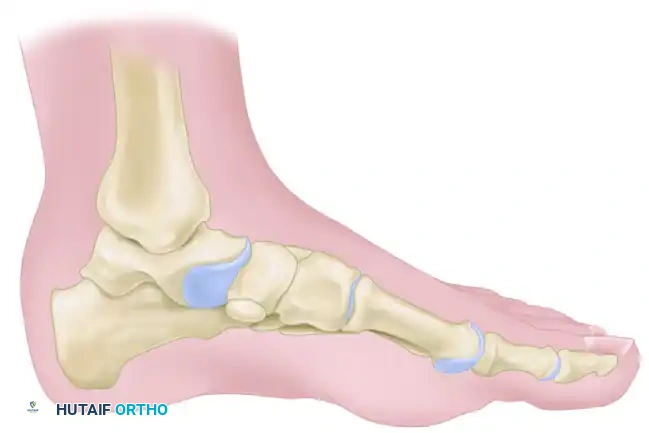

Pathomechanics of the Accessory Navicular

An accessory navicular is a secondary center of ossification that fails to unite with the primary navicular bone. It is present in approximately 10-14% of the population. When symptomatic, the PTT, which often inserts anomalously into this accessory ossicle, exerts a continuous shear force across the synchondrosis during the stance phase of gait. This leads to microfracture, inflammation, and progressive loss of the medial longitudinal arch.

Figure 82-39A (Inset): Location of the accessory navicular and planned incision.

Step 4: Medial Column Flush Resection

Once the accessory fragment is removed, the remaining medial tuberosity of the primary navicular often remains excessively prominent. Use an osteotome or oscillating saw to resect the medial prominence of the navicular so that it is perfectly flush with the adjacent medial cuneiform and the head of the talus. This prevents postoperative shoe-wear irritation.

Figure 82-39D: Accessory navicular removed and the tuberosity of the navicular cut flush with the adjacent cuneiform and talus.

Figure 82-39 (Continued): Final anatomical alignment demonstrating the flush medial column.